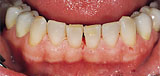

Teeth before treatment with KaVo prophylaxis products Teeth after treatment with KaVo prophylaxis products